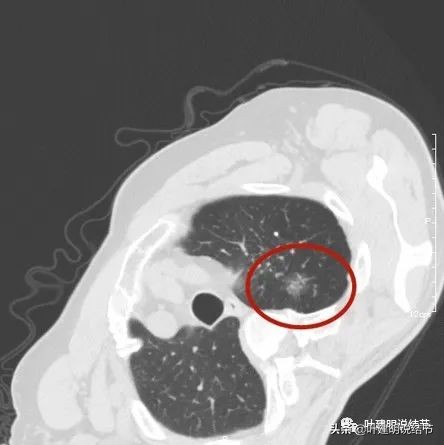

以上诸图是病灶4:考虑囊腔型肺癌可能性大,壁厚薄不均,内壁不光滑,有血管进入病灶,有少许密度偏高的成分,但纵隔窗上未见,不是真正意义上的实性成分。